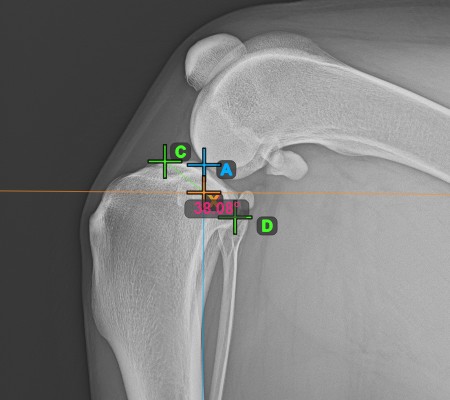

Complete the TPA Angle by marking the most caudal point of the tibial head (tibial plateau). The TPA Angle is automatically calculated as the angle between the line connecting the two points on the tibial plateau and the perpendicular line to the long axis of the tibia.

The image below depicts the usual placement of the most caudal point on the tibial plateau and the automatically calculated TPA Angle measurement.